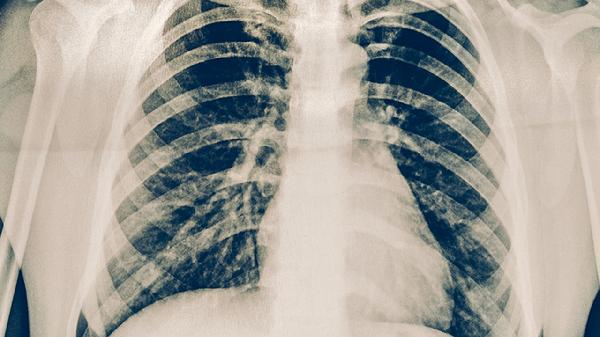

肺癌术后患者通过定期CT复查可以清晰观察到手术区域的变化情况。胸部CT能够显示肺组织修复过程中的结构改变,帮助判断是否存在局部复发迹象。高分辨率CT可检测到毫米级别的微小病灶,对于早期发现肿瘤复发具有重要价值。术后首次CT检查通常在出院前或术后1个月进行,用于评估手术切除范围是否充分以及有无术后并发症。后续随访中CT检查可动态观察纵隔淋巴结状态,及时发现可能出现的淋巴结转移。多层螺旋CT还能重建三维图像,更准确地评估残余肺功能状态。对于接受亚肺叶切除的患者,CT检查可监测保留肺段的代偿性膨胀情况。

肺癌术后复查CT需要关注手术残端有无增厚或新发结节,这些可能是局部复发的征兆。增强CT检查有助于鉴别术后瘢痕组织与肿瘤复发,通过观察病灶的强化特点进行判断。对于接受靶向治疗的患者,CT随访可评估靶病灶的变化情况,为疗效评价提供客观依据。低剂量CT适用于需要长期随访的患者,能在保证图像质量的同时减少辐射暴露。PET-CT可作为CT检查的补充手段,当CT发现可疑病灶但难以定性时,PET-CT能提供代谢信息辅助诊断。术后CT随访发现孤立性转移灶时,可能为患者争取再次手术或局部治疗的机会。